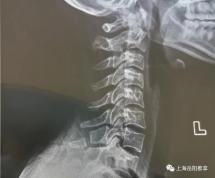

门诊遇到颈椎不好、初次就诊的患者,临床医师一般会让他先拍摄颈椎X线片,再决定如何治疗。很多人拍完片,听到医师告诉他“颈椎曲度(弧度)消失”“颈椎变直了”或者是“颈椎曲度反弓”后,一下子着了慌,开始担心起来:颈椎曲度是怎么消失的?对我以后会有什么影响?消失的曲度还能回来吗?

脊柱的生理曲度并非一出生就有的。刚出生时,人体脊柱是一个开口向身体前侧的“C”形。婴儿在学习爬行和抬头的过程中,颈椎的生理曲度逐渐形成,在颈部呈现出一个开口向身体背侧的“C”形。在学习站立和行走的过程中,腰椎的生理曲度也逐渐形成。一般要到1岁半的时候,脊柱才基本完成了生理曲度的发育,形成了我们所称的“S”形的脊柱。